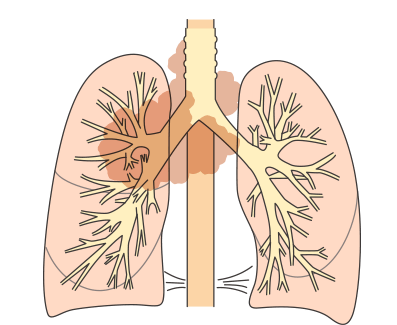

限局型と進展型の違い

がんの広がりによって限局型と進展型に分類され、それぞれに適した治療方法が選択されます。

限局型

<状態>

がんが放射線療法の可能な範囲にとどまっている状態をいいます。

- ・がんが原発巣(最初にがんができたところ)と同じ側の肺にとどまっており、胸腔や心臓に「悪性胸水」「悪性心嚢水」と呼ばれる体液がみられない場合。

- ・同じ側のリンパ節転移(鎖骨上、縦隔、肺門リンパ節)と、反対側の縦隔リンパ節への転移がみられる場合も含む。

限局型小細胞肺がんの病変の範囲

進展型

<状態>

放射線を照射できる範囲を越えてがんがひろがっている状態をいいます。

- ・肺以外の臓器に転移している場合

- ・原発巣以外の肺に転移している場合

- ・悪性胸水、悪性心嚢水がたまっている場合

- ・原発巣と反対側の肺門リンパ節に転移している場合

進展型小細胞肺がんの病変の範囲

IIIA期(ステージ3):局所進行がんの初期

IIIA期

TNM分類でⅢA期と分類された肺がんは、転移はないものの、肺局所で進行している進行がんの初期段階です。

局所進展型あるいは局所進行肺がんといわれることもあります。

図は、原発巣と同じ側の縦隔リンパ節に転移がある例です(N2)。

IIIB・IIIC期(ステージ3):局所進行がん

IIIB期

IIIC期

TNM分類でⅢB・ⅢC期と分類された肺がんは、ⅢA期よりさらに進行した状態の局所進行がんとされています。原発巣側の肺外にリンパ節転移が生じています(N2またはN3)。手術ですべてを取り切ることは難しく、手術をしてもがんが残ってしまう可能性が高いことから、基本的に手術はおこないません。